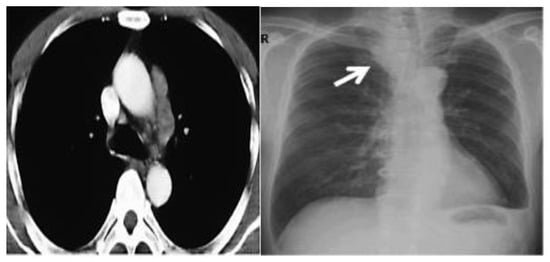

In April 2020, a 59-year-old smoker patient visited our department due to dyspnea and dysphagia.

The patient’s history and physical examination as well as recent imaging evaluation should be well evaluated. Chest CT is the key imaging modality for evaluating lung tumor size and the location of lesions. Because of the complaint also of dysphagia, we conducted a CT scan of the chest, abdomen, and pelvis with means of contrast. A biopsy was taken as advised by [52]. The presence of small cell lung cancer, stage IVA (T4 N3 M1a) was confirmed. PET-CT and CT scans show images of a hypermetabolic left pulmonary hilar tumor (Figure 2).

Figure 2. CT scan (left) and Pet-CT (right) images of hypermetabolic left pulmonary hilar tumor from a female SCC patient.